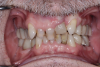

(1.) Pretreatment retracted view of a 16-year-old female patient who presented with generalized spacing between her maxillary anterior teeth. because she was still in her growth phase, milled composite veneers were planned as a transitional treatment. These would be replaced with definitive ceramic veneers once her growth phase was completed.

Figure 1